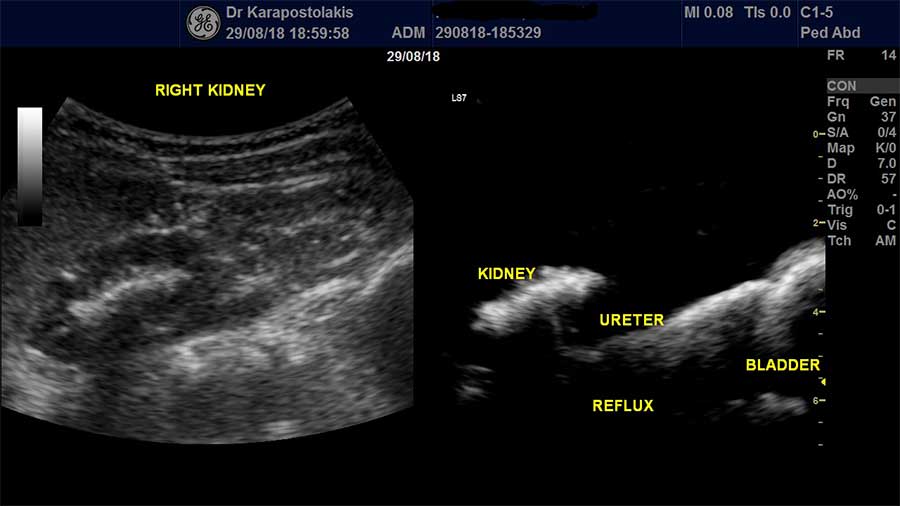

- Υπερηχογραφική κυστεογραφία με σκιαγραφικό υπερήχων (για κυστεοουρητηρική παλινδρόμηση)

Στο Ιατρείο Υπερήχων Παιδιών & Ενηλίκων πραγματοποιείται εδώ και 3 χρόνια μετά από εξειδικευμένη εκπαίδευση σε διεθνές αναγνωρισμένο κέντρο του εξωτερικού, η Υπερηχογραφική Κυστεογραφία (VUS) ως διαγνωστική μέθοδος για την ανίχνευση πιθανής κυστεοουρητηρικής παλινδρόμησης (ΚΟΥΠ) χωρίς ακτινοβολία, με τη χρήση σκιαγραφικής ουσίας υπερήχων. H εξέταση αυτή εμφανίζει την ίδια και μερικές φορές μεγαλύτερη ευαισθησία στην ανίχνευση ΚΟΥΠ από την κλασσική μέθοδο σύμφωνα με τη βιβλιογραφία.

Σημειώνεται ότι στο Ιατρείο Υπερήχων τηρούνται όλες οι απαραίτητες προϋποθέσεις ώστε η Υπερηχογραφική Κυστεογραφία (VUS) να διενεργηθεί με απόλυτη ασφάλεια για το βρέφος, παιδί και το αποτέλεσμα να έχει το μεγαλύτερο βαθμό αξιοπιστίας.